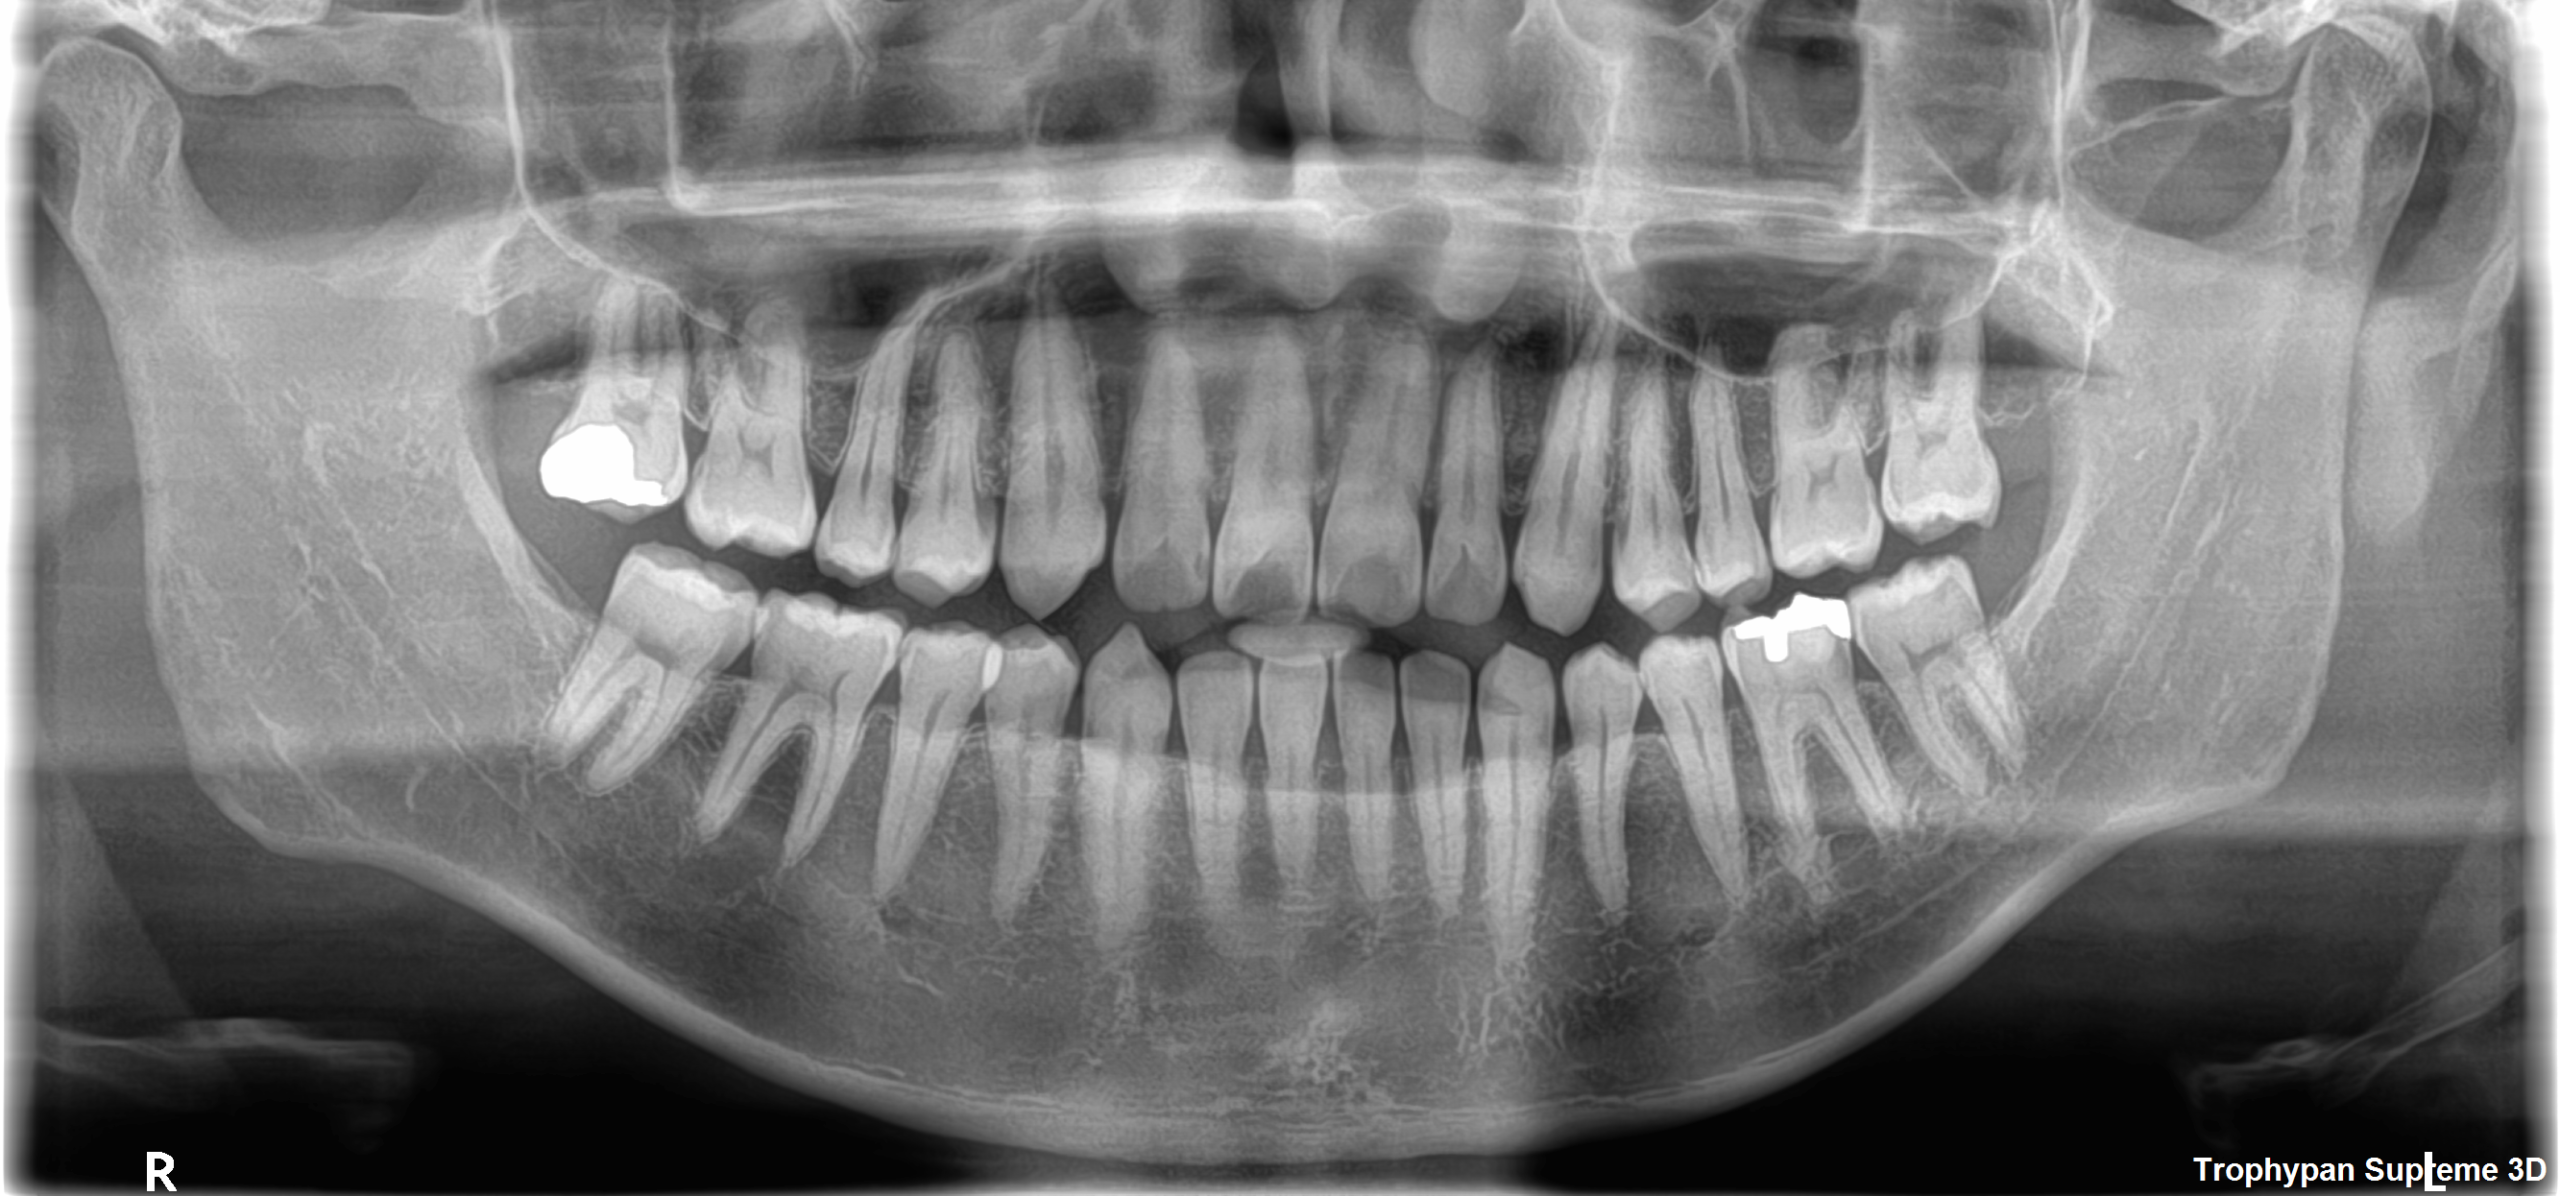

①パノラマ写真

親知らずの数・向きや、歯の本数が合っているかなど、歯や骨の情報を知るために撮影します。